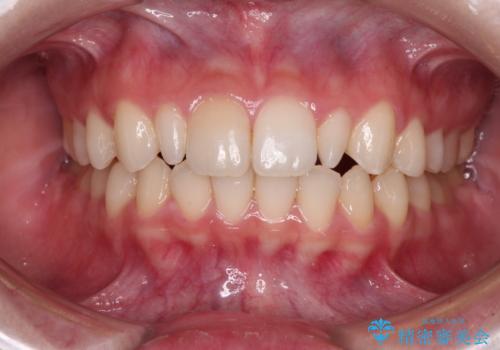

気になる出っ歯をインビザラインで改善

- 上の前歯が出っ歯であることを気にして来院された患者様です。

上の歯列全体が前方に突出している咬み合わせであったので、事前に補助装置を用いて、上の歯列全体を後方に移動させ、その後上下歯列をインビザラインで整えることとしました。

治療期間は長くなりましたが、出っ歯が改善することができました。

治療を行いながら、果たして奥歯の咬み合わせを改善することができるのかという不安はありましたが、結果としては理想的な咬合を獲得することができました。

口が閉じやすくなり、患者様には大変満足していただきました。